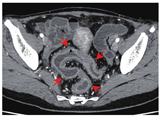

与结肠型CD相比,UC患者的病变更多表现为连续性分布(80%比57.5%,P = 0.03)、肠壁呈环周均匀性增厚(77.5%比47.5%,P = 0.006),较少出现肠周炎性渗出(20.0%比67.5%,P<0.001)及肛瘘(10.0%比57.5%,P<0.001),差异均有统计学意义。结肠型CD病变肠壁厚度大于UC患者[(9.5 ± 3.4) mm比(8.1 ± 2.2) mm,P = 0.024],更多表现为不同部位的严重程度不一致(75.0%比45.0%,P = 0.006),差异均有统计学意义,见图1,图2,图3,图4。两组患者其余影像学特征差异无统计学意义(P均>0.05)。见表3。

与UC相比,结肠型CD更多表现为病变节段性分布、非对称性肠壁增厚,厚度多厚于UC,肠周炎性渗出及肛瘘也更加常见,多变量回归模型也提示肠周炎性渗出、肛瘘是诊断结肠型CD的有效预测因子。多节段性病变是CD的典型影像学表现,而UC患者更多表现为病变连续性分布,与既往报道的一致[15]。另外,结肠型CD患者以非对称性肠壁增厚为主,提示即使位于同一部位的病变,CD患者仍具有跳跃性的趋势,从而表现为影像学上单一节段的肠壁厚薄不均匀。这同样解释了结肠型CD患者在不同部位表现为炎症反应程度不一致的可能原因,而UC患者则更常出现结肠病变相一致的影像学表现。然而,进一步多因素回归分析显示,节段性病变与非对称病变并不能作为诊断结肠型CD的独立预测因子。在肠壁厚度上,结肠型CD患者厚于UC患者,我们认为这与CD表现为累及肠壁全层的透壁性炎症相关,除黏膜层受累之外,黏膜下层炎性水肿也常常同时出现,更有甚者累及肌层之外。而UC仅累及肠壁的黏膜层,病变浸润深度往往表浅,造成了两者影像学上的厚度差异,虽然多因素回归模型显示肠壁增厚没有显著差异(P = 0.051),但肠壁厚度越大,诊断结肠型CD仍具一定的优势比。Ellrichmann等[16]通过超声内镜比较UC与CD的结肠病变厚度,证实了CD黏膜下层厚度高于UC(P = 0.0001),CD平均肠壁厚度稍高于UC,但两者之间差异无统计学意义(P = 0.06)。本研究中,结肠型CD常伴有肠周炎性渗出,而UC患者少见,这或许依赖于两者在病理上累及肠壁的深度及层次有所不同,从而导致继发肠周炎性渗出改变的差异。肠周炎性渗出的出现明显提高了诊断结肠型CD的价值,这也是多因素回归模型中诊断结肠型CD的重要预测因子。另外,结肠型CD患者有50%以上会合并肛瘘,而UC少见,肛瘘是本研究中回归模型的关键预测因子,具有高优势比,其中的具体机制尚不明确,但肛瘘的出现对结肠型CD的诊断具有重要的参考价值。这也提示我们,IBD患者在行腹部检查时,放射医师应尽量覆盖肛管的扫描,这将进一步有助于临床诊断。